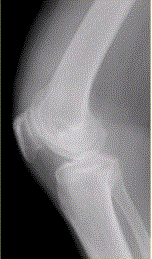

问题 患者女,54岁,右膝关节痛。实验室检查:类风湿因子阳性,除外膝关节类风湿性关节炎。X线检查结果如下图。 类风湿性关节炎早期的病理改变是

选项 A.关节软骨变性 B.关节滑膜增生 C.滑膜血管翼形成 D.关节强直 E.关节边缘骨侵蚀

答案 B